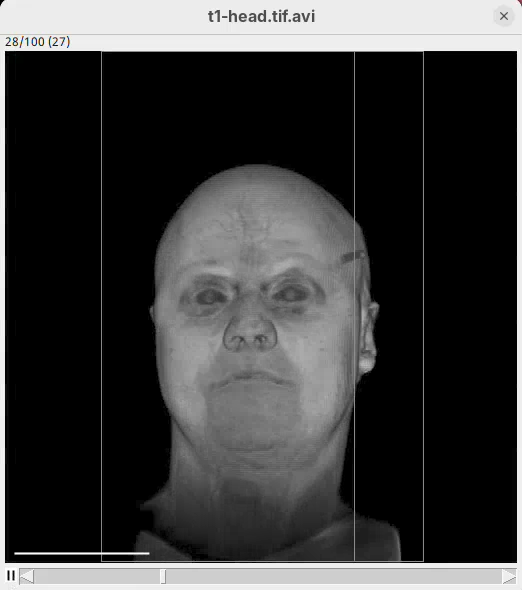

We will begin by visualizing an MRI dataset of a human head that is bundled in Fiji.

- Go to

File>Open Samples>T1 Head (16-bits).

- Increase the zoom to 200% for better visualization.

Orthogonal Views

Orthogonal Views is a tool that shows the optical sections through the orthogonal planes of XY: XZ and YZ. It is an easy and quick way to get a sense of the tridimensionality of your dataset. Whenever I’m opening a dataset for the first time I use Orthogonal Views. To activate it:

- Click on

Image>Stacks>Orthogonal Views(or pressCtrl+Shift+H). - The XZ and YZ panels will open next to your XY stack.

- The yellow lines are synchronized between the panels.

- Click around the different parts of the head to inspect the same position under different angles.

Orthogonal Views is a great way to start understanding your 3D data.